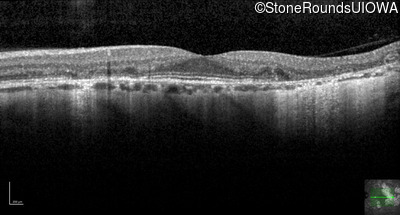

Optical Coherence Tomography - Right - 20/20

Exemplar / OCT Stack